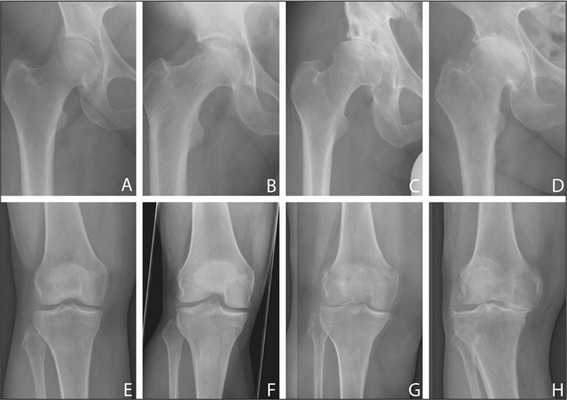

Сравнение двух типов операций.

В ретроспективном анализе сравнивали, сколько людей вернулось в любительский спорт после ТЭКС (65% от общего числа) и одномыщелкового эндопротезирования (93%). К тому же, после полной замены сустава люди были склонны выбирать вид спорта со сниженной физической активностью (в 91% случаев - боулинг).